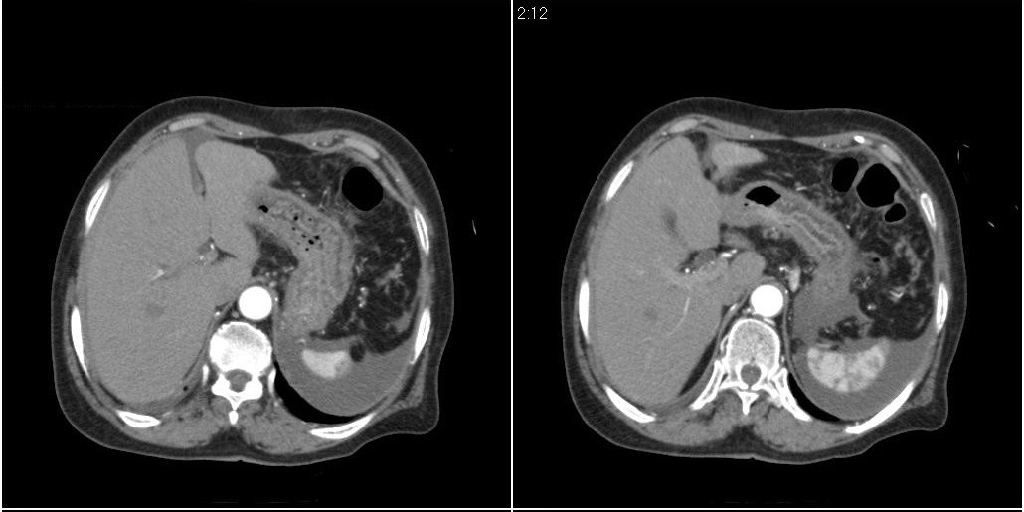

胆囊有问题么,是结石么?胆囊内异常密度平扫30hu左右,增强各期无变化。

胆囊内稍高密度影,无强化,胆囊壁增厚,周围见低密度影,右侧膈肌角及脾周水样密度,支持胆囊泥沙样结石,胆囊炎、胆囊窝积液,胸腹水。

1)胆囊炎,胆结石;胆囊新生物待排。2)胆囊窝积液。3)腹水。4)右侧少量胸腔积液。